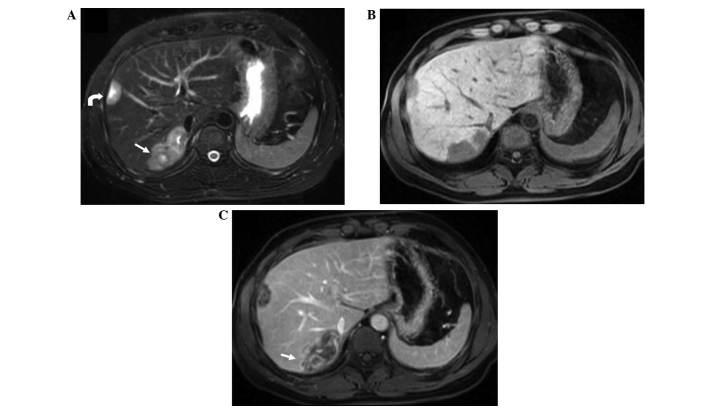

To investigate the typical magnetic resonance imaging (MRI) and computed tomography (CT) features of hepatic epithelioid hemangioendothelioma (HEH), the CT and MRI findings of 14 histopathologically confirmed cases of HEH were retrospectively analyzed. Non-contrast and dynamic contrast-enhanced scans were conducted in all cases. A total of 229 lesions were detected in the 14 cases. All cases were classified as one of three types: (i) Solitary nodular type (1 case, 7%); (ii) multifocal nodular type (11 cases, 79%); or (iii) diffuse type (2 cases, 14%). The diameter of the lesions ranged from 5 to 105 mm. For the first two types (solitary and multifocal nodular types), the CT findings included low density lesions with clear margins on non-contrast scans, centripetal enhancement in arterial phase, and homogeneous enhancement in the portal venous and delay phases. The findings of non-contrast MRI scans for these two types included low signal intensity on T1-weighted images, heterogeneous high signal intensity on T2-weighted images, and heterogeneous high signal intensity on diffusion-weighted images. The lesions were predominantly located in submarginal areas. On contrast-enhanced MRI, the findings for the first two types included peripheral ring-like enhancement with a central low signal intensity ('black target-like' sign) and a central enhanced core surrounded by a low signal intensity halo ('white target-like' sign). The findings for the third HEH type (diffuse type) on CT and MRI scans included low density or heterogeneous signal intensity lesions involving regions of part or the whole liver, coalescent lesions ('strip-like' sign), and gradual enhancement along central vessels ('lollipop' sign). Collectively, these findings indicate that the 'white target-like' sign, 'black target-like' sign, 'lollipop' sign and 'strip-like' sign, in addition to capsular contraction and submarginal location, on CT and MRI imaging may have implications for the diagnosis of HEH. Furthermore, a variety of MRI sequences may provide additional information for the differential diagnosis of HEH.

为研究肝上皮样血管内皮瘤(HEH)的典型磁共振成像(MRI)及计算机断层扫描(CT)特征,对14例经组织病理学确诊的HEH患者的CT和MRI表现进行回顾性分析。所有病例均行平扫及动态增强扫描。14例患者共检出229个病灶。所有病例分为以下三种类型之一:(i)孤立结节型(1例,7%);(ii)多灶结节型(11例,79%);或(iii)弥漫型(2例,14%)。病灶直径5~105 mm。前两种类型(孤立结节型和多灶结节型),CT表现为平扫低密度病灶,边界清晰,动脉期向心性强化,门静脉期及延迟期均匀强化。这两种类型的MRI平扫表现为T1加权像低信号,T2加权像不均匀高信号,扩散加权像不均匀高信号。病灶主要位于边缘下区域。增强MRI表现为前两种类型有周边环形强化,中央低信号(“黑靶征”)及中央强化灶周围有低信号晕(“白靶征”)。第三种HEH类型(弥漫型)的CT和MRI表现为低密度或信号不均匀的病灶累及部分或整个肝脏区域,融合病灶(“条带征”),沿中央血管逐渐强化(“棒棒糖征”)。总体而言,这些表现表明CT和MRI成像上的“白靶征”“黑靶征”“棒棒糖征”及“条带征”,以及包膜皱缩和边缘下位置,可能对HEH的诊断有提示意义。此外,多种MRI序列可为HEH的鉴别诊断提供更多信息。